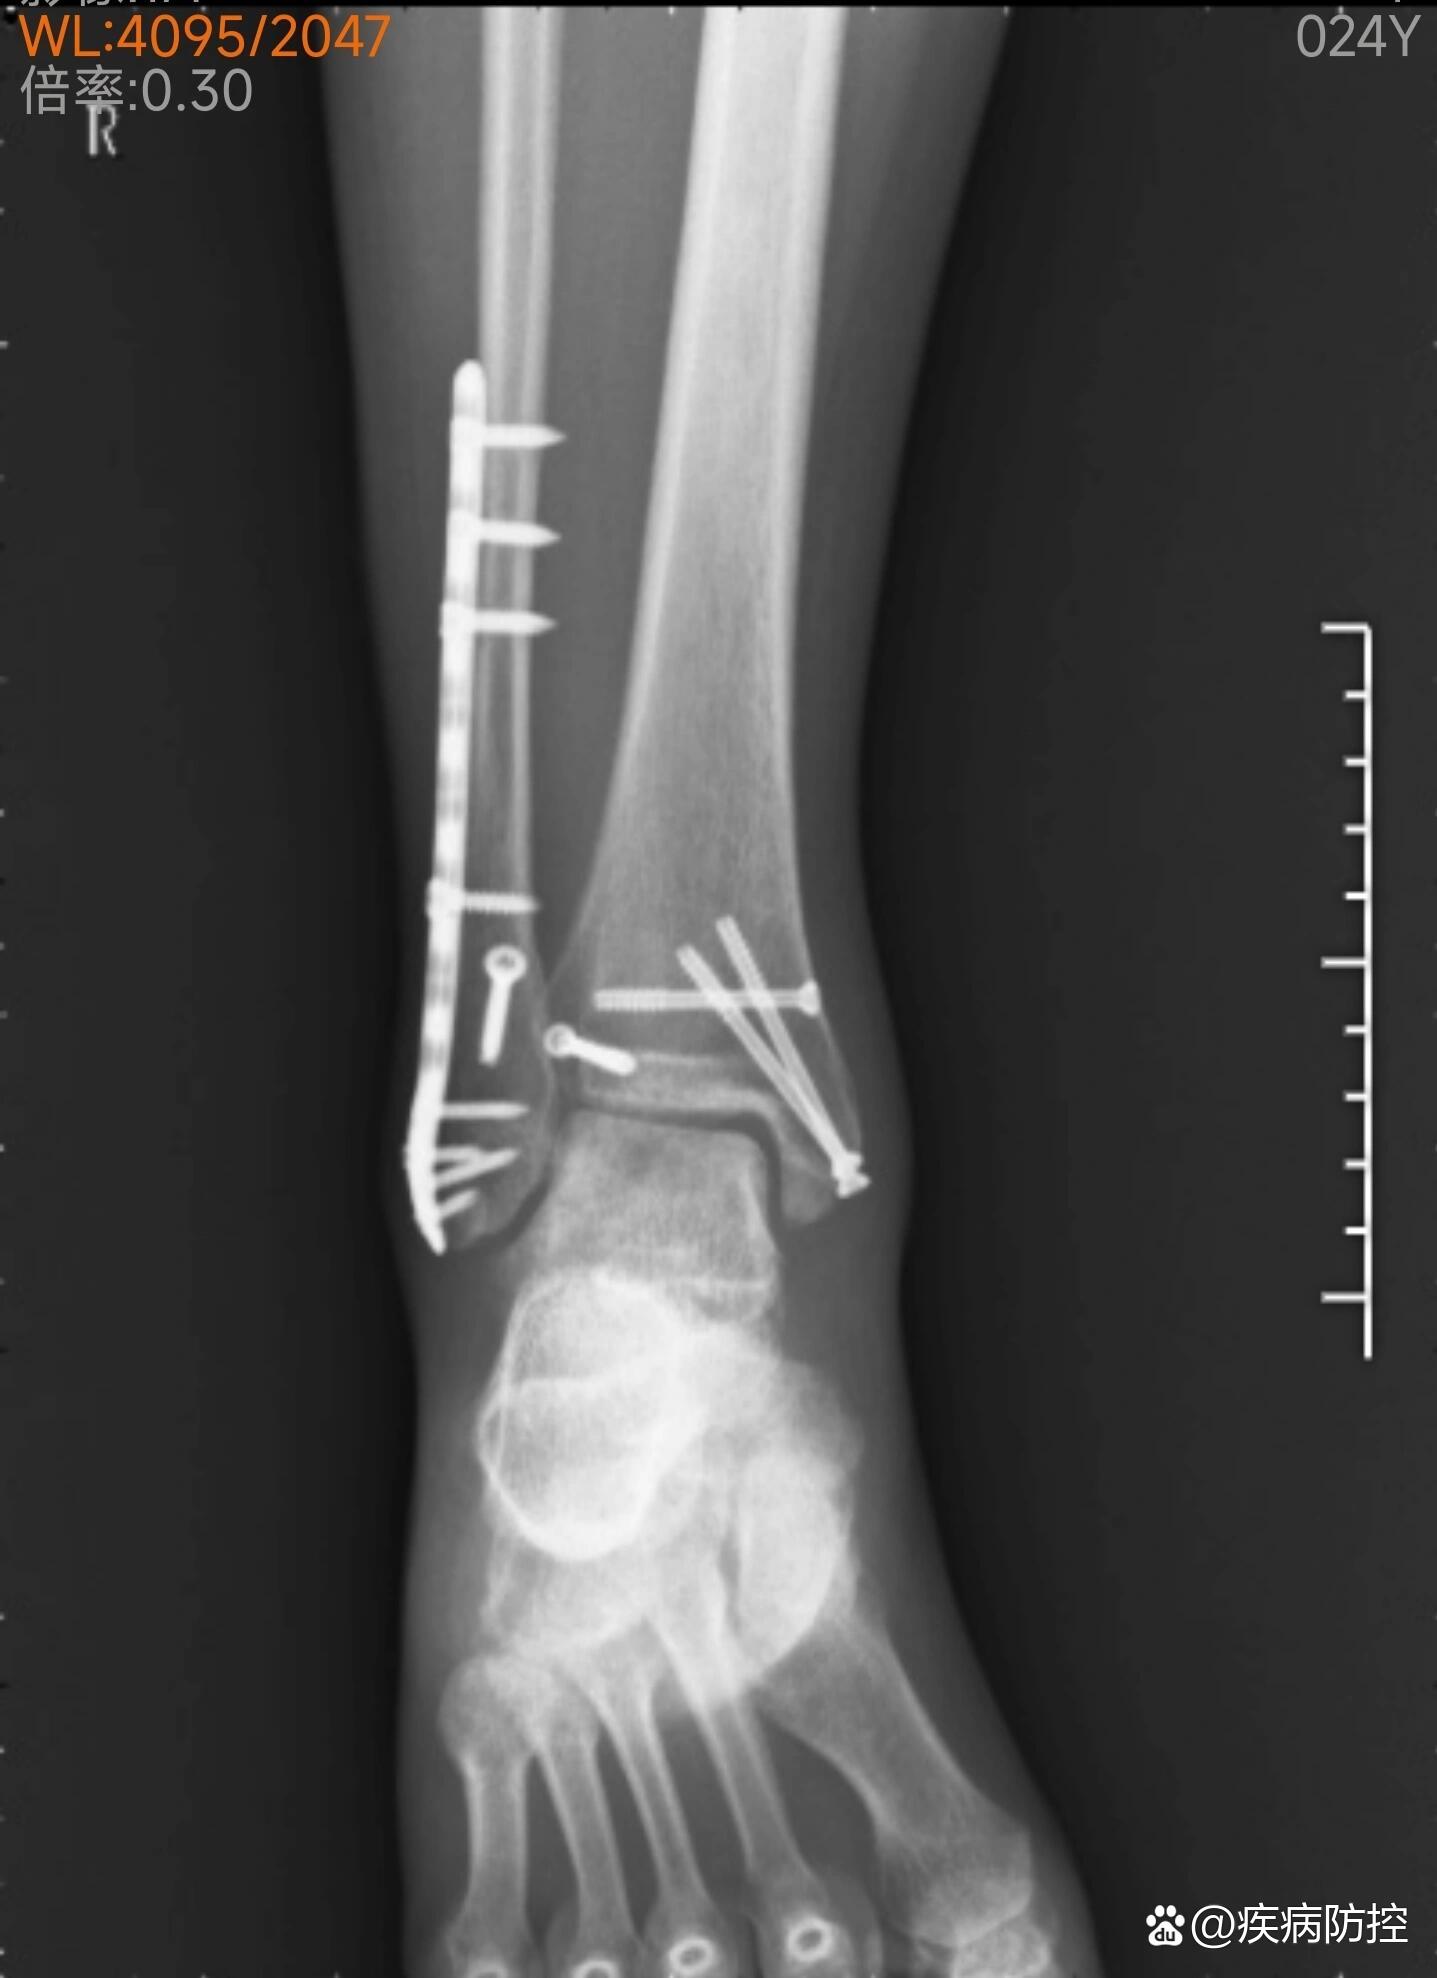

踝关节骨折多久才走路

恢复期关键注意事项1营养支持保证每日蛋白质摄入如瘦肉鱼蛋类,补充维生素D和钙牛奶豆制品,促进骨愈合2康复训练术后24周可进行踝关节被动活动如足趾屈伸,6周后逐步过渡到主动活动,避免关节僵硬3负重原则从部分负重如双拐辅...